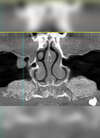

L’image 3D de contrôle post-opératoire montre le gain obtenu par le soulèvement sinusien

L’image en 3 dimensions indique que la hauteur disponible d’os est de 7 mm

La simulation implantaire indique que la hauteur d’os à gagner est de 3 mm pour placer un implant de 10 mm